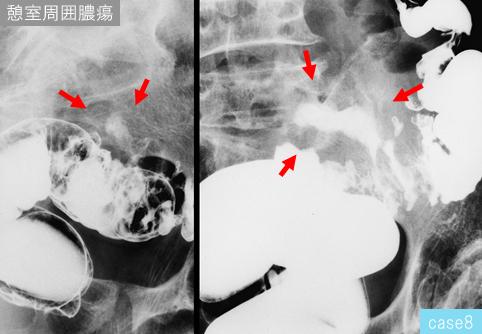

Diseases related to the diveruculosis of the large intestine.

[ Image ID:12029 ]

others/

Location

Large intestine(Colon)/Sigmoid colon

X-ray